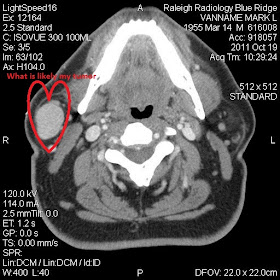

For this reason, administration of contrast material is helpful because cysts usually enhance on their periphery, whereas pleomorphic adenomas enhance solidly (Figs 3c, 7b).Now, with a little annotation of my own, here's a picture of the mass in my parotid gland.

Yes, ladies and gentlemen, I believe we have a tumor. I stress that word "believe" because, of course, everything I've just done is a bit of a mug's game. I have no training. I am self-diagnosing using an image I'm not even supposed to have seen. I've read multiple studies about how bad people are at self-diagnosing using Web techniques; I've heard figures of over 90% of the people being wrong, and almost everyone tending to choose a bad outcome.